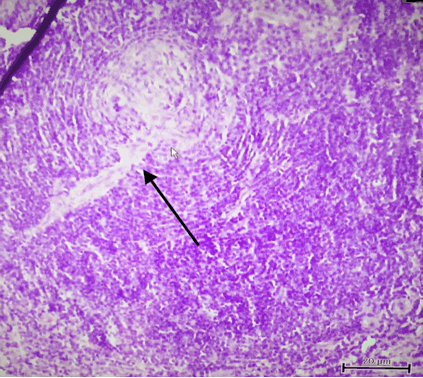

An 18-year-old female with no co-morbidities, presented with a swelling in the right side of the neck for the past two years, which had increased over the past one month. There was no pain over the swelling, no complaints of difficulty in eating or swallowing food. There was no history of fever, night sweats, or weight loss. There was no history of any other such swellings in any part of her body. Physical examination revealed a firm level II cervical lymph node in the right side of her neck. Contrast-enhanced computed tomography scan, of the neck showed a well-defined right cervical lymph node of 4 x 3 cm (Figure 1). She underwent excision biopsy of the lymph node at another institution and was referred to our center for further evaluation and management. Computed tomography scan of the thorax, abdomen and pelvis showed no other significant lymphadenopathy. HIV, HBsAg and Anti-HCV antibodies were negative. Bone marrow aspiration and biopsy were normal. Histopathology of the same showed a characteristic onion skin appearance of follicles with two germinal centres within the same follicle surrounded by a marked mantle layer hyperplasia (Figure 2). There was also presence of the pathognomonic "Lollipop Lesions" (Figure 3) which are formed due to penetration of sclerotic blood vessels into the atrophic germinal centers. These features were consistent with the diagnosis of the hyaline vascular variant of unicentric Castleman's disease. As whole node excision was done and she had no evidence of disease elsewhere in the body, she was kept under follow-up.

Figure 2: Characteristic histopathological appearance of two germinal centers (arrows) within a single follicle, surrounded by marked mantle cell hyperplasia).

The hyaline vascular variant of Castleman's disease is characterized by the presence of abnormal follicles with atrophic germinal centers surrounded by wide mantle zones consisting of small lymphocytes [2]. A characteristic feature is the presence of two adjacent germinal centers surrounded by a single, wide mantle zone. These are called double germinal centers. The germinal centers are usually depleted of lymphocytes and are replaced with follicular dendritic cells arranged in a concentric manner producing an onion-skin appearance (Figure 2). The interfollicular tissue contains many small sclerotic blood vessels These are often seen penetrating up to the centre of the regressed germinal centers, producing a pathognomonic "lollipop lesion" [1] [2] [13].